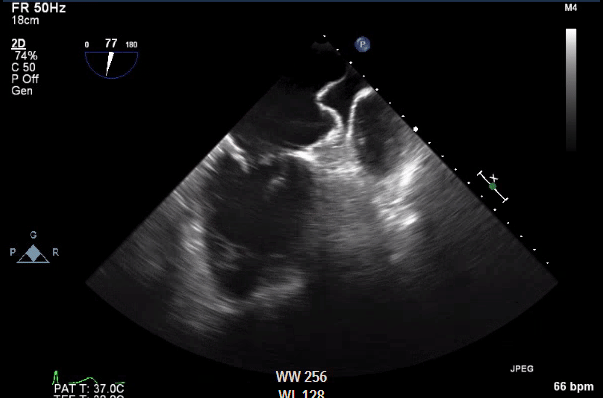

Watchmen flx is superior to previous gen watchman device. More malleable for difficult appendages.

Nah.... scale is turned way down like 30 cm/s. No VC/device leak at 0,45,90 and 135. Clean fluoro. Mitral shoulder tucked in as beat as possible. Probably would have been a real challange with a watchman 2.5.

Ummm... yeah. What’s so bad about taking someone off of anticoagulants? 75 y/o with history of falls? Should have seen my 4th watchman patient yesterday. Kind of like this but worse.